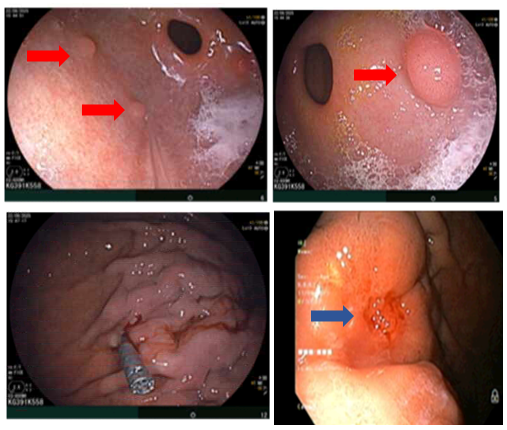

Hình 1

. Hình ảnh dày thành dạ dày đoạn thân vị. Ổ tiêu xương có viền đặc xương chỏm xương đùi phải (vòng tròn màu cam)

- Cắt lớp vi tính ổ bụng: Bờ cong lớn đoạn thân vị dạ dày thành dày không đều, vị trí dày nhất ~12mm,trên đoạn dài ~55mm, tăng ngấm thuốc sau tiêm, vài hạch lân cận lớn nhất đường kính ~ 10mm (>4 hạch). Ổ tiêu xương có viền đặc xương chỏm xương đùi bên phải đường kính 4mm.